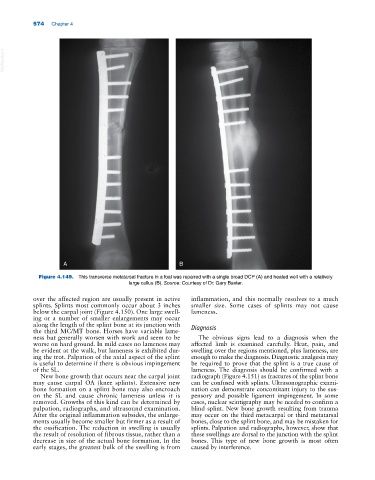

Figure 4.149. This transverse metatarsal fracture in a foal was repaired with a single broad DCP (A) and healed well with a relatively

large callus (B). Source: Courtesy of Dr. Gary Baxter.